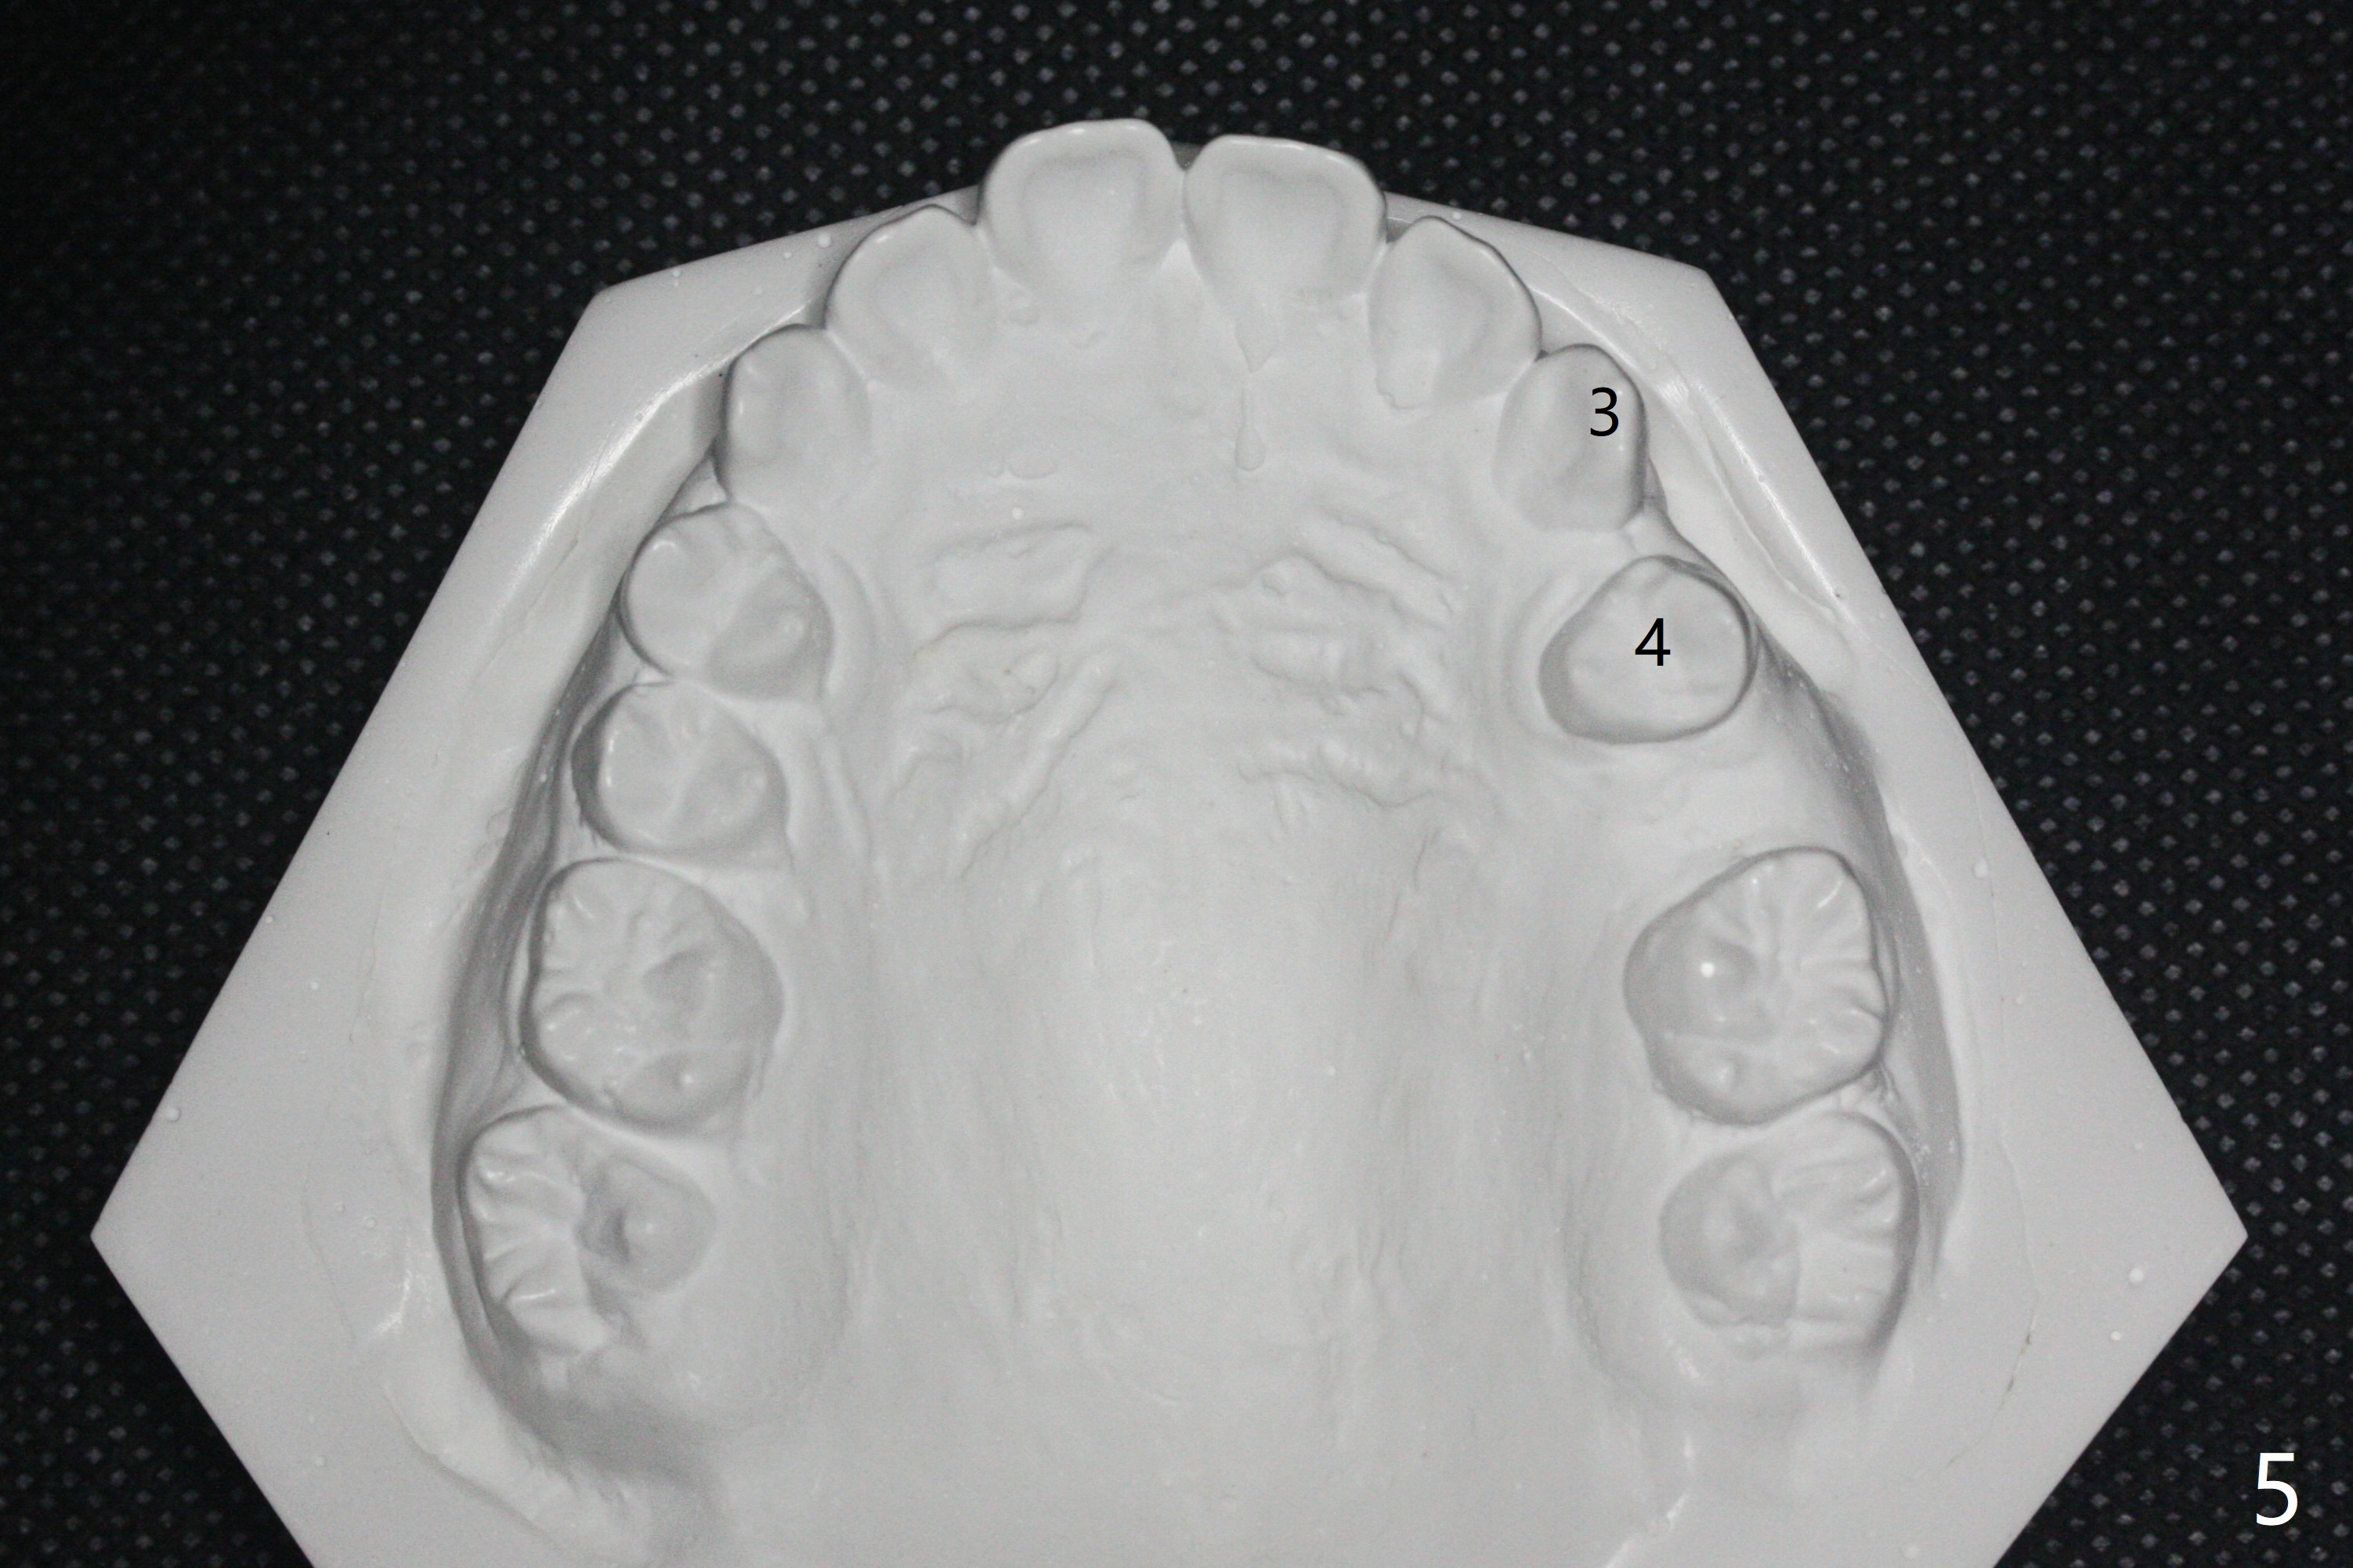

One-year-8-month orthodontic treatment reduces anterior overjet (Fig.1 (double arrows),1', with facial profile improvement), corrects right 1st molar cross bite (Fig.2,2') and dental midlines (Fig.3,3'), closes the diastema between UL3 and 4, extrudes UL5 (Fig.4,5,4',5'), and increases space for future implant at LL4 (Fig.6,6'). In fact large arches with distemata make the treatment possible! Extrusion of UL5 leads to root development (Fig.7, 7' (R)). The increased space at LL4 (Fig.7' *) appears insufficient for an implant.